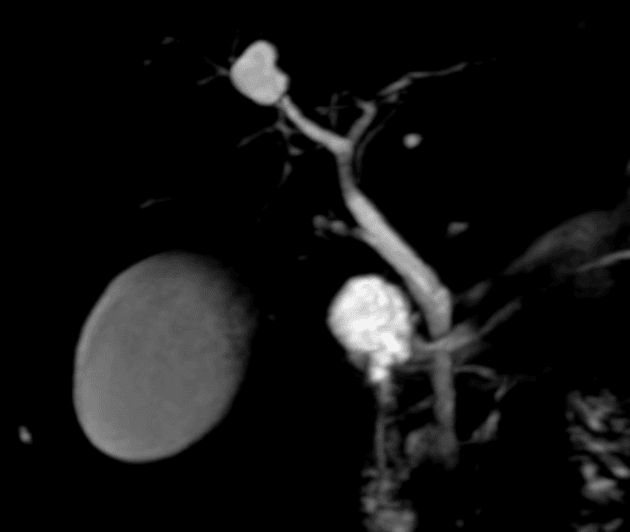

- Túi mật chứa nhiều viên sỏi, được hiển thị rõ trên các chuỗi xung MRI khác nhau.

- Các sỏi được xác định rõ nhất trên hình ảnh trọng T2 và MRCP do chúng hiện lên như các vùng giảm tín hiệu (hypointense) trong lòng túi mật.

- Hình ảnh trọng T2 và MRCP là các kỹ thuật hình ảnh lý tưởng để phát hiện sỏi túi mật và sỏi ống mật do đặc tính không tín hiệu (no signal) của sỏi trên các chuỗi xung này.

- MRCP đặc biệt hữu ích trong việc đánh giá đoạn xa ống mật chủ và điểm đổ vào tá tràng, nơi mà các phương pháp khác có thể khó quan sát.

Sỏi túi mật (cholelithiasis) trên nền hình ảnh MRCP.

- "Sỏi túi mật hiện diện như các khuyết thiếu tín hiệu giảm đậm độ trong lòng túi mật trên hình ảnh trọng T2 và MRCP."

- "MRCP có độ nhạy cao trong việc phát hiện sỏi đường mật và là tiêu chuẩn vàng không xâm lấn để đánh giá hệ thống đường mật."

Sỏi túi mật, hay còn gọi là cholelithiasis, thường được phát hiện tình cờ hoặc ở bệnh nhân có các triệu chứng như đau quặn mật hoặc rối loạn tiêu hóa. MRCP là phương tiện hình ảnh không xâm lấn, hiệu quả cao, sử dụng các chuỗi xung trọng T2 để hiển thị dịch đứng yên trong hệ thống đường mật. Các viên sỏi hiện lên như những khuyết thiếu tín hiệu giảm đậm độ rõ ràng trong lòng túi mật hoặc ống mật. Khác với siêu âm, MRCP cung cấp hình ảnh rõ nét toàn bộ hệ thống đường mật, kể cả đoạn cuối ống mật chủ, mà không bị ảnh hưởng bởi hơi ruột hay thể trạng bệnh nhân. MRCP không cần thuốc cản quang hay tia bức xạ, do đó rất phù hợp để đánh giá các bệnh lý đường mật nghi ngờ khi siêu âm không kết luận được. Tuy nhiên, MRCP không đánh giá được chức năng túi mật hay tình trạng viêm thành túi mật, nên việc kết hợp với lâm sàng là cần thiết.